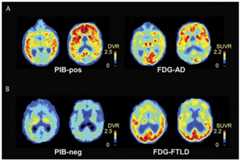

Atrophy or hypometabolism of the right frontal or right temporal lobe is the hallmark neuroimaging finding in patients with bvFTD (Case 5-1). Bilateral frontal lobe involvement may also be seen, although when atrophy is observed in the dominant hemisphere, language symptoms are typically also present (see later discussion of semantic variant PPA and nonfluent agrammatic variant PPA). Patterns of atrophy in other brain regions vary according to mutation type. Patients withC9ORF72 expanded repeats demonstrate atrophy predominantly in the frontal lobes, with some atrophy also observed in the anterior temporal lobes, parietal lobes, occipital lobes, and cerebellum and thalamus; inMAPT mutations, atrophy is greatest in the anteromedial temporal lobes; patients with bvFTD andGRN mutations show temporal, insular, and parietal lobe atrophy.10,11 On fluorodeoxyglucose positron emission tomography (FDG-PET) imaging, hypometabolism in the right temporal or right or bilateral frontal lobes is suggestive of FTD (Figure 5-212). Patterns of frontal or anterior temporal hypoperfusion with preserved parietal signal on SPECT can distinguish FTD from AD with a sensitivity and specificity of approximately 80%.13 Similar patterns of hypometabolism on FDG-PET imaging show approximately 90% diagnostic accuracy when distinguishing FTD from AD.14 PET amyloid imaging shows a similarly high accuracy of distinguishing FTD from AD, with patients with FTD typically showing low levels of amyloid binding on PET (amyloid negative), while patients with AD show elevated amyloid binding (amyloid positive).12 Several PET tau ligands are currently under investigation in FTD but are not validated to date.

Figure 5-2.

Example of amyloid (Pittsburgh compound B [PiB]) and fluorodeoxyglucose positron emission tomography (FDG-PET) scans demonstrating typical patterns of diffuse amyloid deposition and temporal and parietal hypometabolism in Alzheimer disease (A) in contrast to the absence of amyloid deposition and presence of frontal hypometabolism in a patient with frontotemporal dementia–motor neuron disease, confirmed on autopsy to have frontotemporal lobar degeneration (FTLD) with TDP-43 inclusions (B).

AD = Alzheimer disease; DVR = distribution volume ratio; neg = negative; pos = positive; SUVR = standardized uptake value ratio.

Modified with permission from Rabinovici GD, et al, Neurology.12www.neurology.org/content/77/23/2034.full. © 2011 American Academy of Neurology.